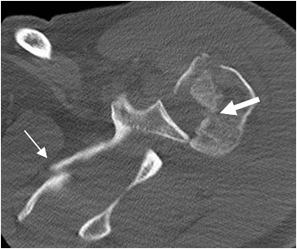

TAC axial. Luxación posterior, con fractura conminuta de la cabeza humeral. (Flecha gruesa). Adicionalmente hay fractura de la escápula. (Flecha delgada).

Fig 51 B. Bankart invertido.

Fig 51 C. Bankart invertido.